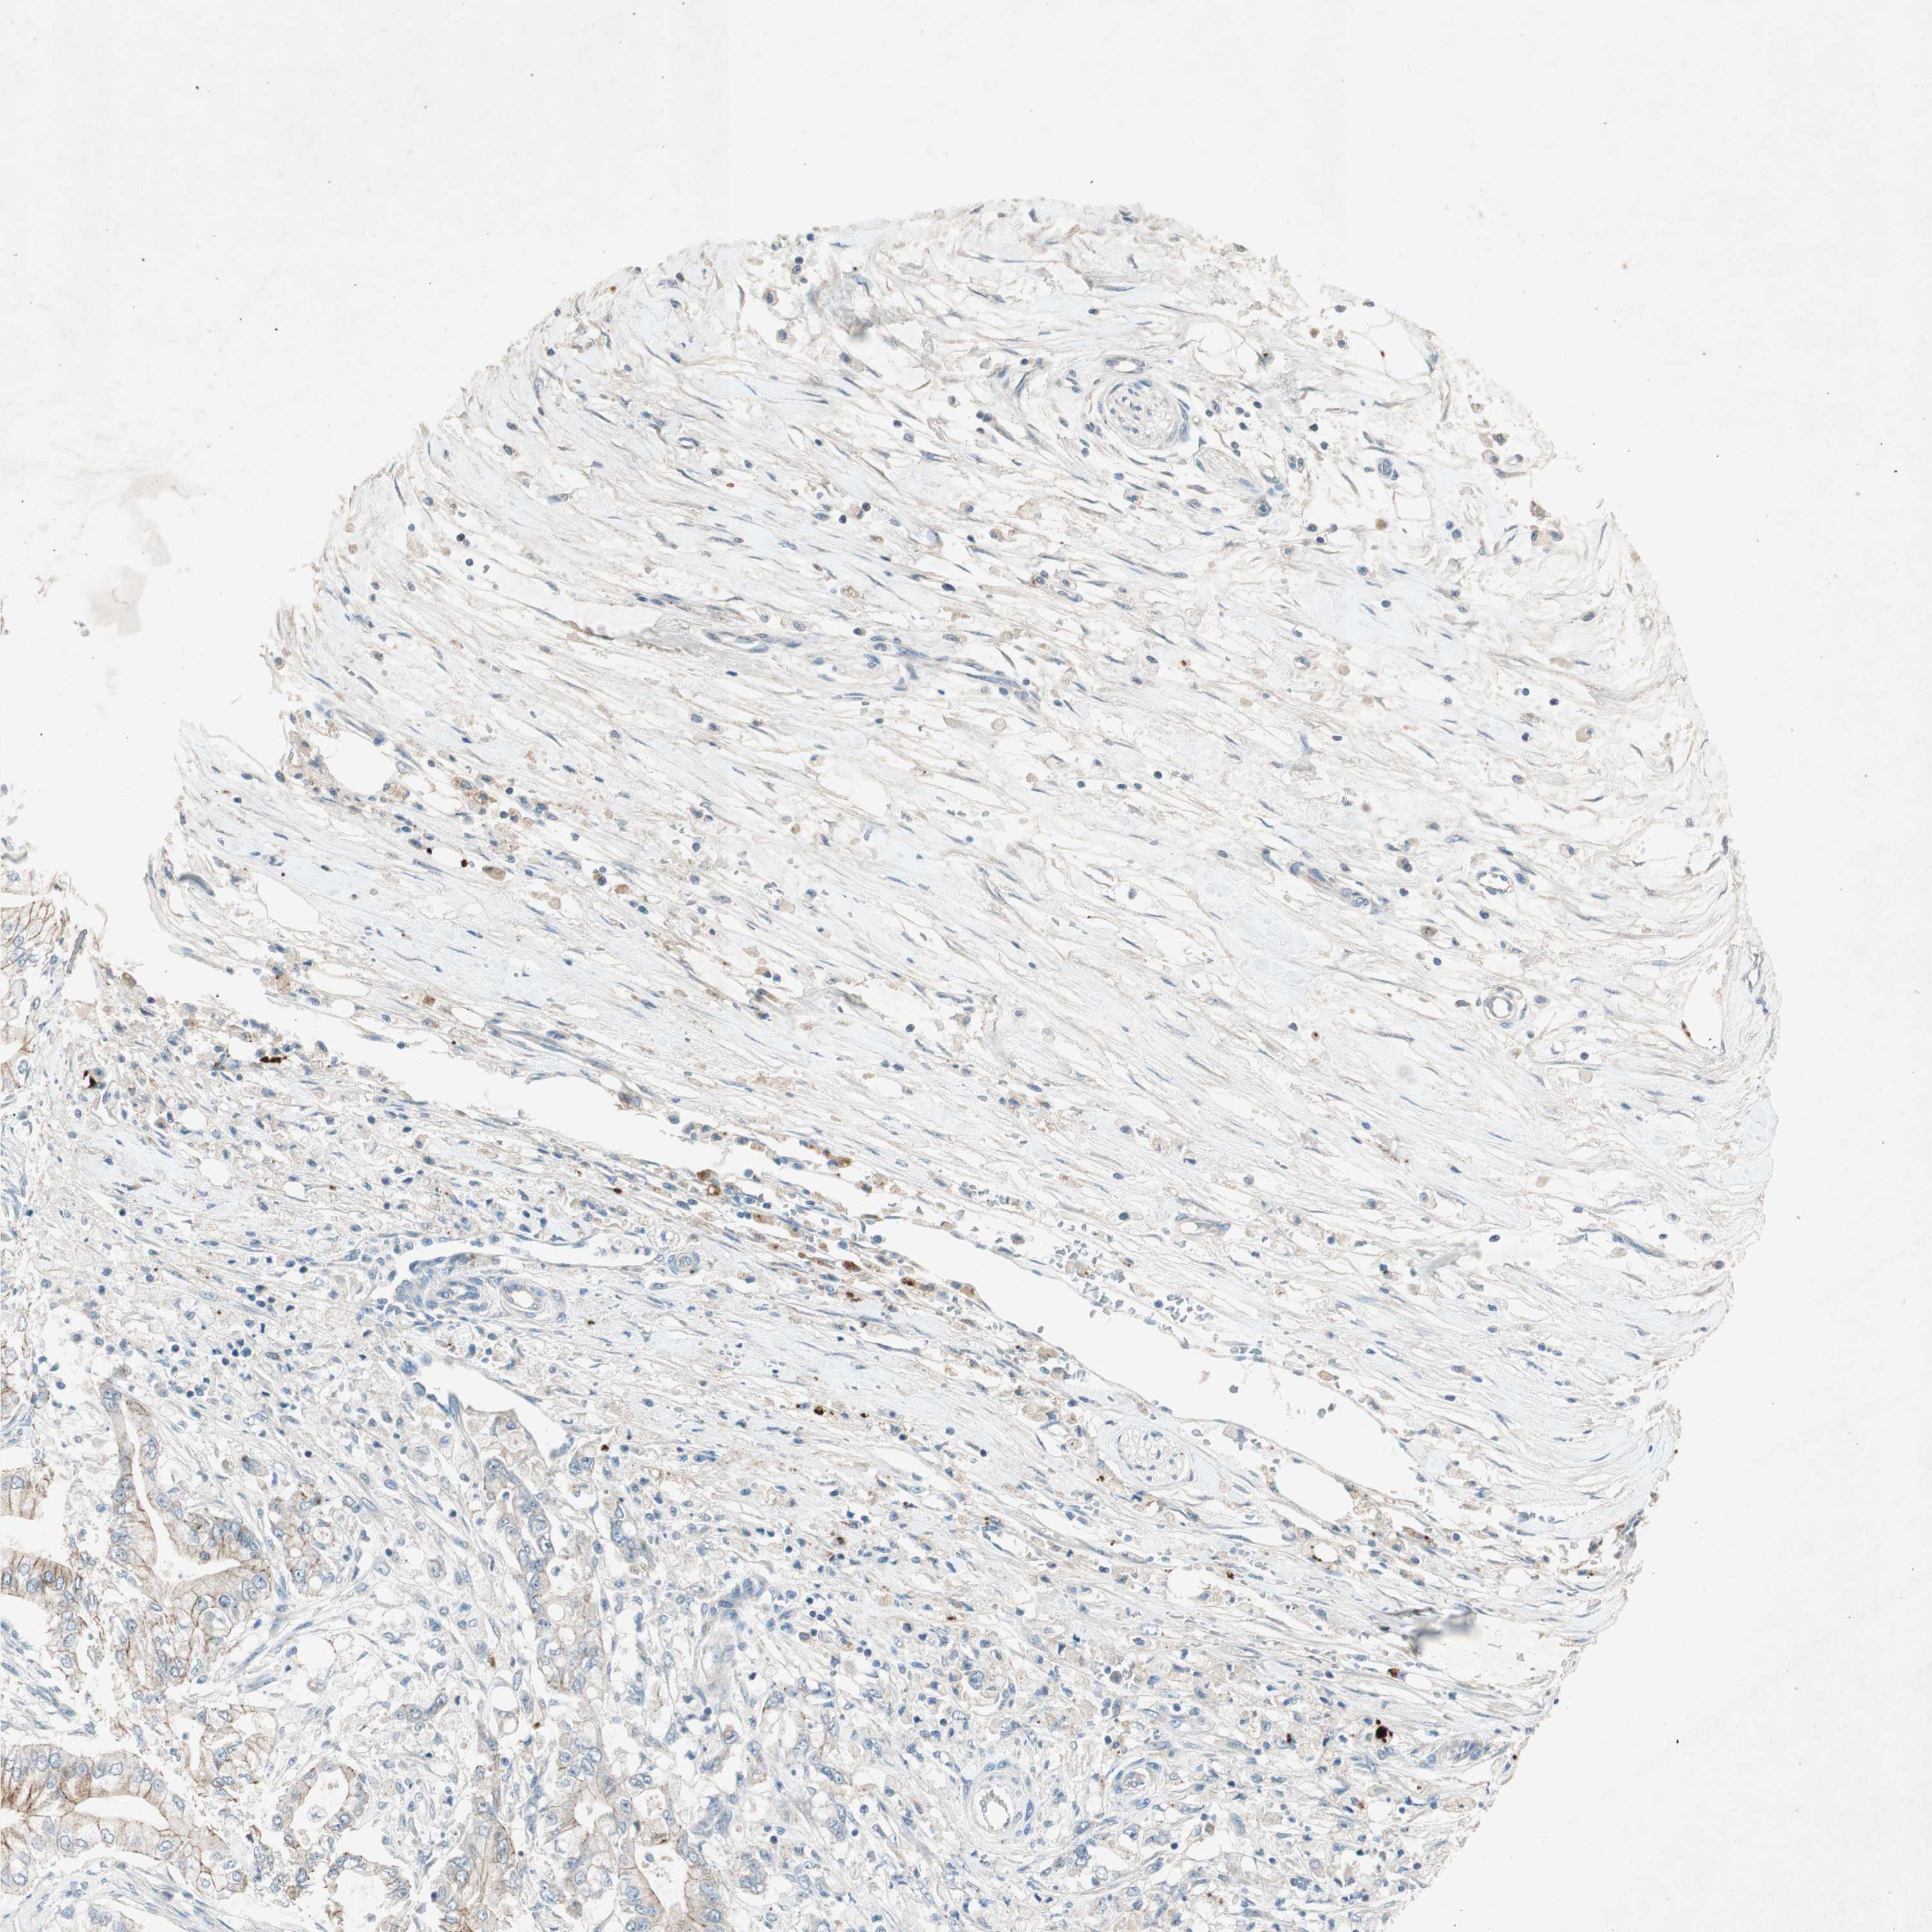

PANCREATIC CANCER - Protein expressioni

A mouse-over function shows sample information and annotation data. Click on an image to view it in a full screen mode. Samples can be filtered based on level of antibody staining by selecting one or several of the following categories: high, medium, low and not detected. The assay and annotation is described here.

Note that samples used for immunohistochemistry by the Human Protein Atlas do not correspond to samples in the TCGA dataset.

Antibody stainingi

Antibody staining in the annotated cell types in the current human tissue is reported as not detected, low, medium, or high, based on conventional immunohistochemistry profiling in selected tissues. This score is based on the combination of the staining intensity and fraction of stained cells.

Each image is clickable and will lead to virtual microscopy that enables deeper exploration of all samples and also displays staining intensity scores, fraction scores and subcellular localization as well as patient and tissue information for each sample.

Antibody HPA006873

Staining

High

Medium

Low

Not detected

Intensity

Strong

Moderate

Weak

Negative

Quantity

>75%

75%-25%

<25%

None

Location

Nuclear

Cytoplasmic/membranous

Cytoplasmic/membranous,nuclear

Adenocarcinoma, NOS

Adenocarcinoma, metastatic, NOS